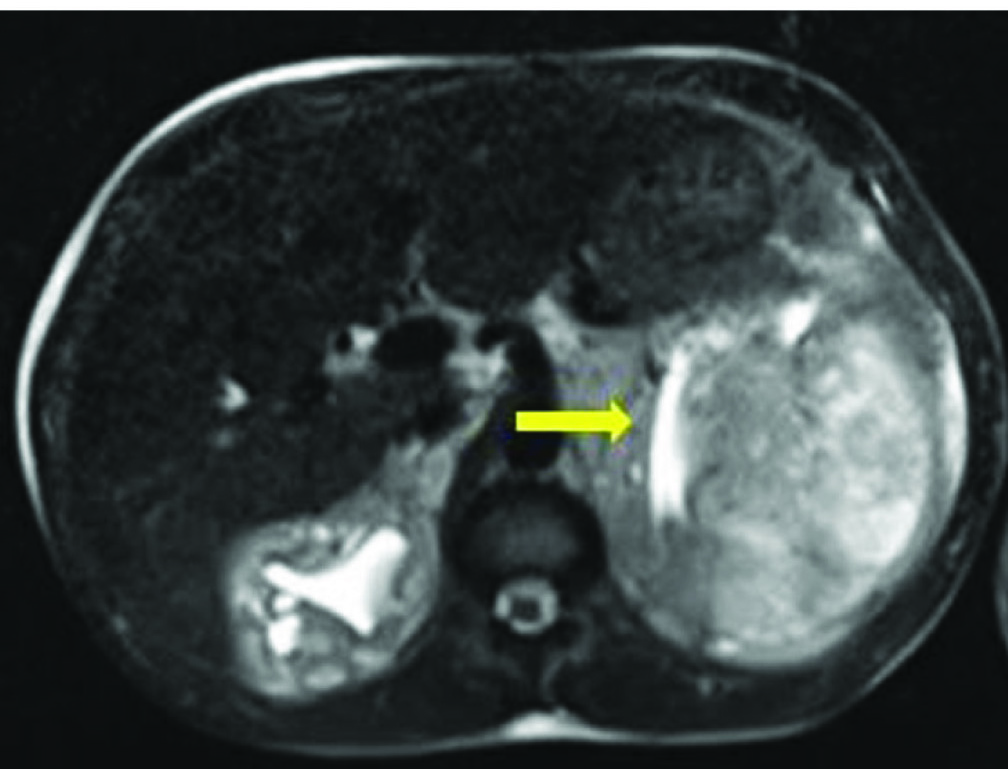

MRI was suggestive of bilateral perirenal haematoma [Table/Fig-3]. After this a CT Angiogram (CTA) was done which revealed left subcapsular haematoma 10.3 x 10.3 cm compressing and displacing the left kidney, fed by capsular branch of the left renal artery [Table/Fig-4]. He also had right perinephric subcapsular haematoma of 3.6 x 3.1 cm. He was managed with three sessions of HD, packed red blood cell transfusions and intravenous antibiotics. As he persisted to have febrile spikes, renal failure and urosepsis, repeat NCCT was done after 10 days which revealed left perinephric abscess. PCD was done with 14F pigtail catheter. Patient improved and his serum creatinine stabilized at 2 mg/dl without haemodialysis. PCD was removed after two weeks and is on regular follow up for six months with stable renal function and his perinephric haematoma have resolved.

MRI suggestive of bilateral perirenal haematoma (arrow showing compressed left kidney).